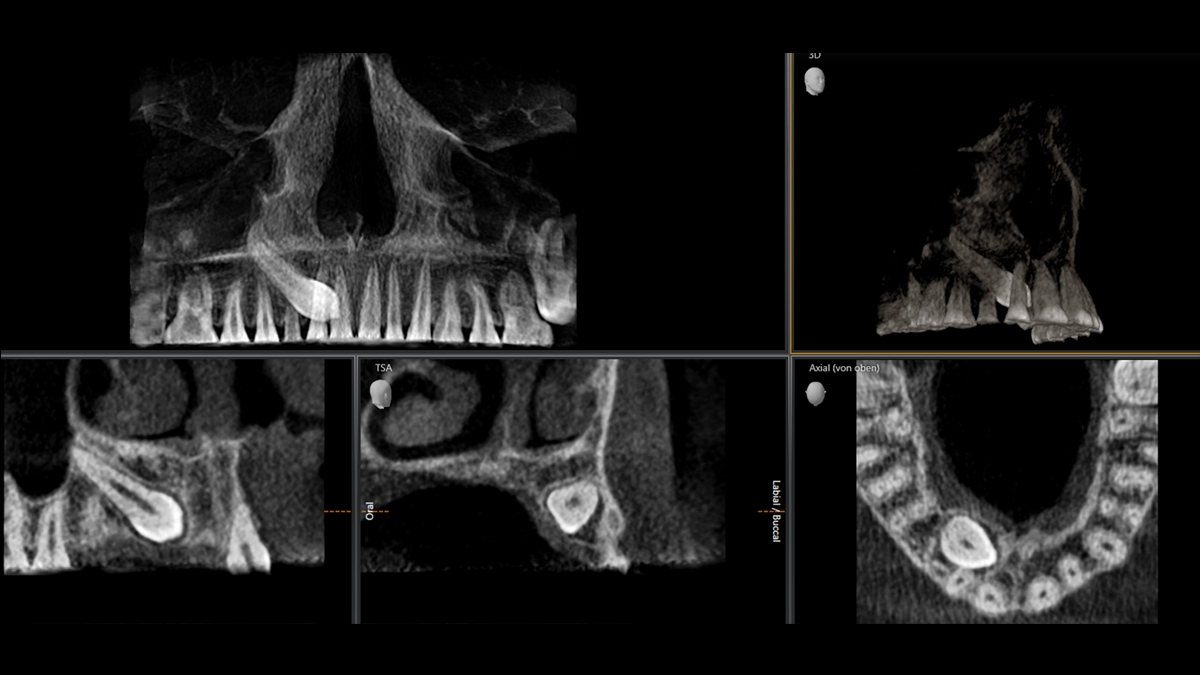

We developed a 10-point concept for easy patient positioning and X-ray imaging. Our concept is primarily about two things: high image quality and comfort for the patient and the assistant. This concept supports and provides the tools needed to ensure high-quality images for treatment analysis and focuses on ergonomics and comfort for the patient and assistant.

The patented bite block technology, for example, automatically establishes the correct inclination of the patient's head, positioning the patient in the occlusal plane, partnering with the 3 point head fixation and firm handles to ensure stable positioning-limiting unnecessary correction scans.